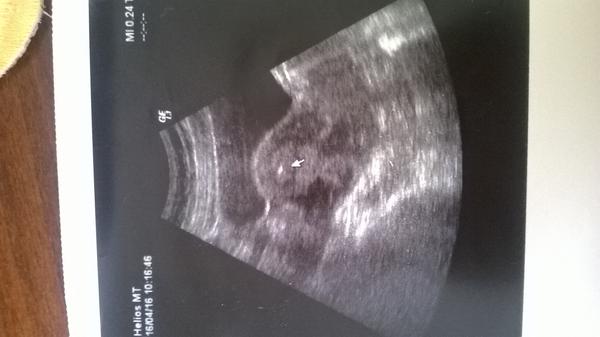

Urcite hned pisem ked budem vediet idem aj na sono aj ked neviem ci by bolo nieco vidno asi nie tak skoro 😉

@aluska1404 možno malinku gulicku gestacny vak bude vidieť ..drz sa a hneď daj vediet 😎

@14nunu10 To iz by mohlo ked bola vkadana blastocysta 6 dnova byt vidno???Asi hej lebo aj pri vklade mi dali obrazocok a tam bola gulocka malinka

@aluska1404 aj mne dali tu fotku pri vklade,ale keď som bola u gyndosa na 13 deň po ET bol vidieť gestacny vak pohladam foto